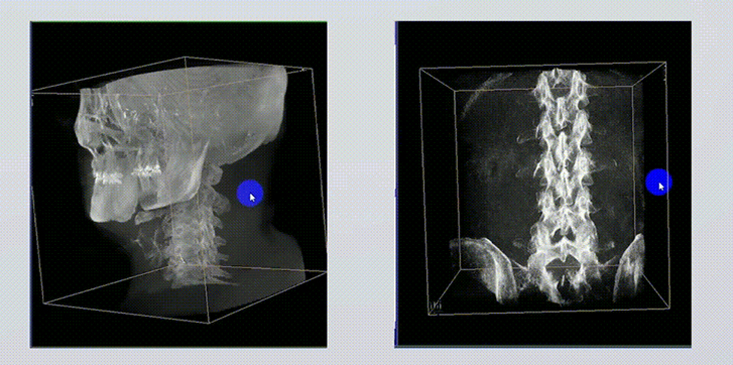

1、術(shù)中實時三維成像

術(shù)中三維成像和橫斷面圖像提供多角度的手術(shù)診斷信息,輔助醫(yī)生進行術(shù)中評估判斷,諸如骨折復(fù)位情況和內(nèi)植入螺釘?shù)某叽绾臀恢?,輔助手術(shù)更好地完成。

2、三維成像視野大

提供更大的術(shù)中三維成像視野,采集更多圖像信息,可一次拍全全段頸椎、全段腰椎、七節(jié)胸椎、雙側(cè)骶髂關(guān)節(jié)、股骨頭及單側(cè)盆骨。